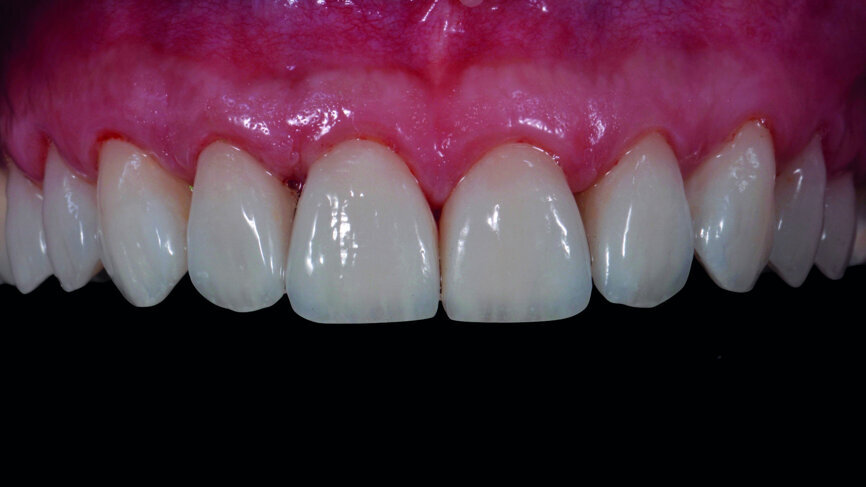

Fig. 16f: Final outcome immediately after removal of the rubber dam.

Fig. 17a: Final outcome one week later.

Fig. 17b: Final outcome one week later, frontal view.

The subjective decision of the clinician and the patient was to cement the feldspathic veneers, owing to slight differences in the length of the central incisors between the two sets. Adhesive procedures followed (Figs. 16a–f), and final intraoral and extraoral photographs were captured one week later (Figs. 17a–e).